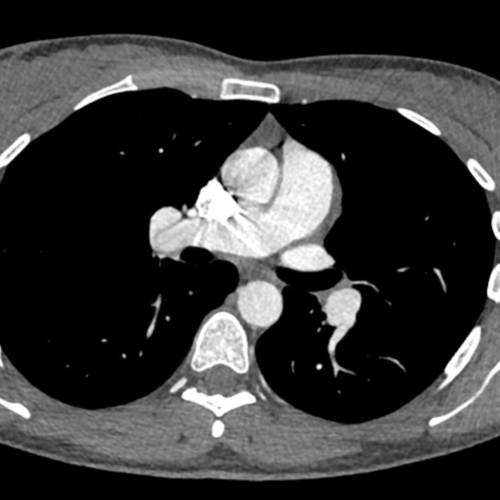

Cet examen est réalisé pour analyser le thorax et notamment les artères pulmonaires et ses branches.

L’ angioTDM thoracique permets également d’analyser les tissus autour du poumon, le médiastin (contient coeur, trachée, gros vaisseaux, oesophage) , la plèvre et les côtes notamment.

Lors de la réalisation de votre angioscanner pulmonaire au centre IMBM à Paris, dans le 18ème, vous serez guidé par le manipulateur en radiologie.  Une injection de produit de contraste iodé est nécessaire. Cela permet de mieux voir les gros vaisseaux, le cœur et le médiastin.